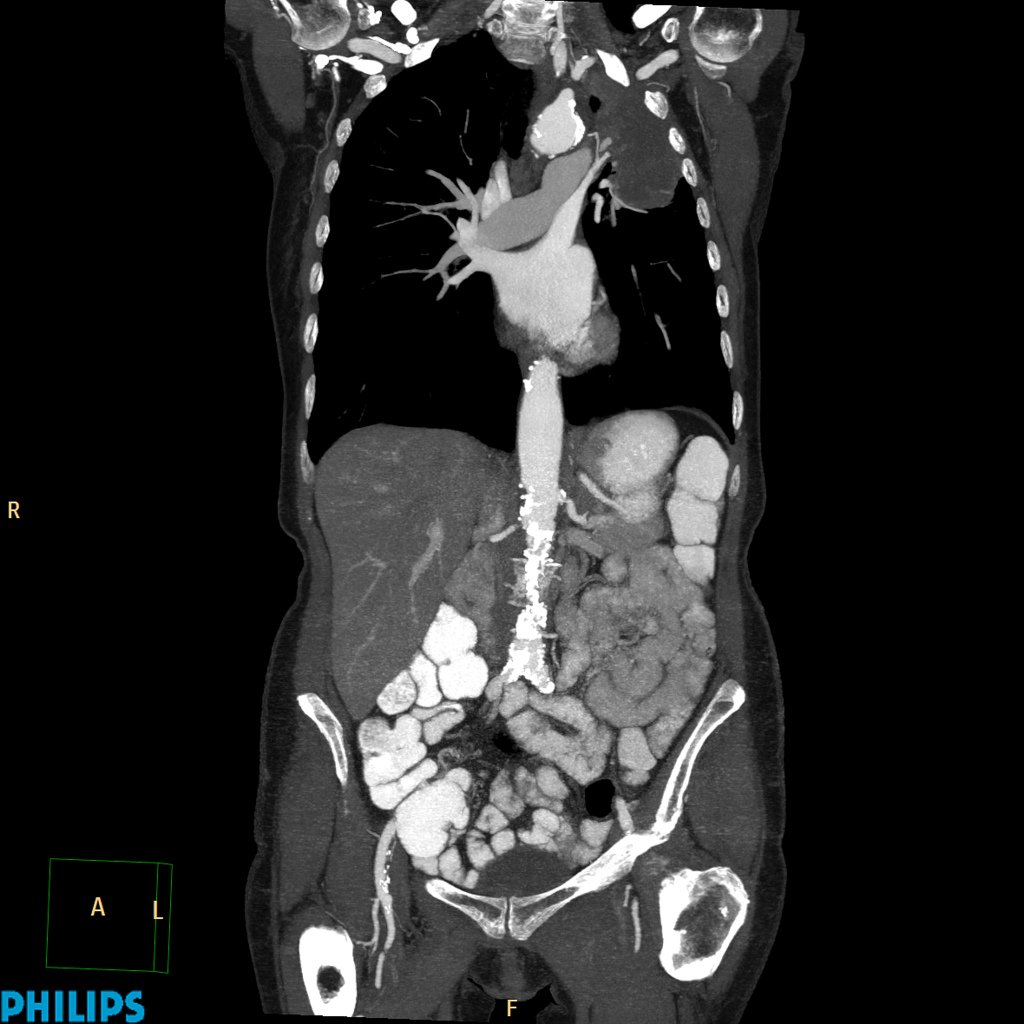

A ct scan can show whether breast cancer has spread to the lungs or liver. Apart from detecting cancers, the process is also used to diagnose various other diseases and is a lifesaving tool for doctors. Ct scan of the abdomen. Early detection and diagnosis of cancer can significantly increase your chances of being treated successfully. For instance, in breast cancer, it cannot detect stage o dcis, nor will is show. Each has its own strengths. Overall, ct scans prove very beneficial when diagnosing cancer as they have a short study time and provide quality images. Ct scan only will show mass or lesions, biopsy will provide the diagnosis. A scanner then detects this substance to produce. Effectiveness of ct scan for pancreatic cancer detection. The accurate depiction of the cancer within the body is. However, there are a few disadvantages that. During the study, the diagnostician can change the thickness of the cut up to 1 mm.

If cancer was detected through the nhs breast screening programme, you may need another mammogram or ultrasound scan. Ct scan of the abdomen. A ct scan is one of the most frequently utilized exams to detect cancer and to show things such as a tumor's shape and size. The ct can detect some masses that would then need further evaluation. Pet/ct scan combinations detect cancer in its earliest stages, when changes are happening at the cellular level.